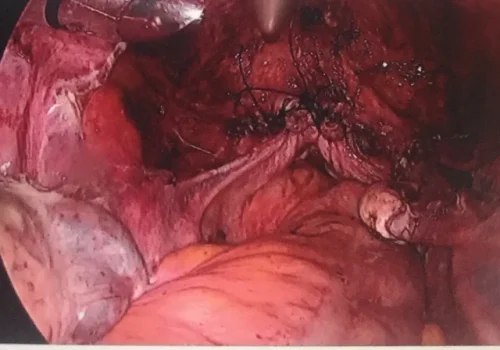

Procedure

She subsequently underwent Total Laparoscopic Hysterectomy.